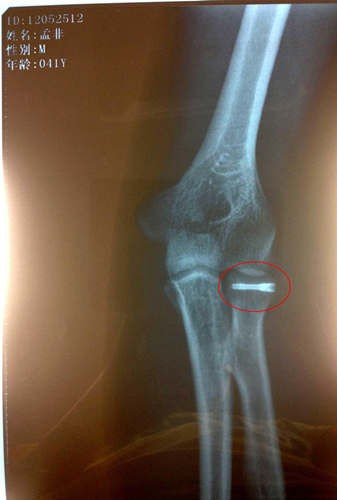

孟非打鋼釘x光片

自孟非不慎跌落舞臺之后,他的傷情也是牽動了無數(shù)人的心。據(jù)悉,在孟非回到南京后立即接受了手術且手術進行地非常成功,術后一直在家中休養(yǎng)。最近傷勢恢復地很好,已經(jīng)不再用石膏和繃帶固定了,而是改成了鈦合金鋼釘固定,上周日“孟非粉絲團”的微博也首度曝光了孟非打著鋼釘?shù)腦光片。根據(jù)目前的情況,醫(yī)生預計傷愈時間會大大縮短。根據(jù)最近錄制計劃,本周末《非誠勿擾》恢復錄制,打著鋼釘?shù)拿戏且灿诮袢罩鼗毓ぷ鲘徫唬鴮τ诿戏潜局艽蛑撫敾貧w錄制,很多人則大贊勞模孟非是“主持人界的鋼鐵俠”

據(jù)了解,確診撓骨骨折的孟非在家中休養(yǎng)已經(jīng)有半個月時間,專心養(yǎng)傷術后恢復情況很好,孟非在家每天要保證一定時間的康復訓練,在家全身心的養(yǎng)傷給了他最大程度的休息,接受手術的左手手臂已不用打著厚厚的石膏,不用吊著繃帶固定,孟非還開玩笑:“現(xiàn)在的醫(yī)療技術很先進,傷口處打上了一根鈦合金的鋼釘,就這樣一處理,然后就不用繃帶石膏里一層外一層的包了。”受傷在家的孟非也難得偷閑,陪陪家人,看看書,溜溜狗。